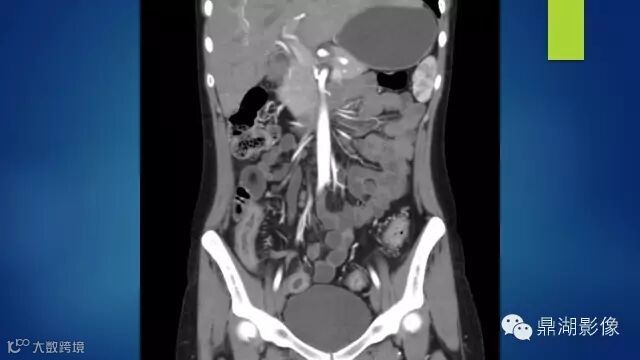

Crohn's disease.

IBD,CD

CD belongs to IBD, right ?

the answer is easy,but today we will learn this diease deeply

There's a contrast uptake ,so I doubt it's ischemia

do you know comb sign?

The comb sign refers to the hypervascular appearance of the mesentery in active Crohn disease.

It is the comb sign the most specific sign for crohn's disease.